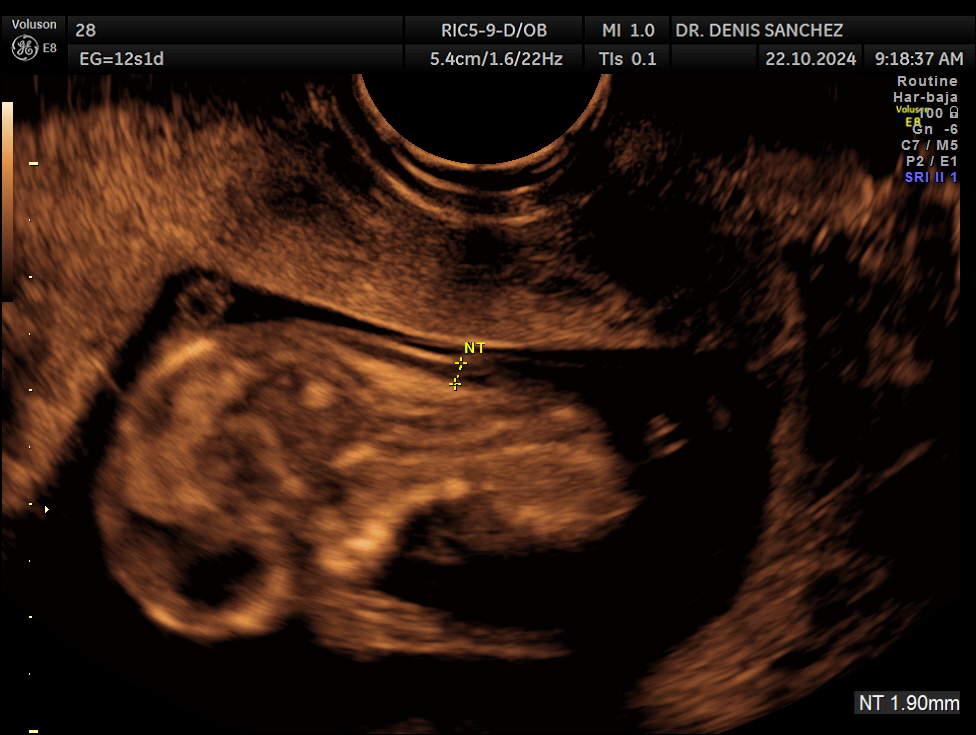

Translucencia nucal (TN): mide el grosor del espacio en la nuca del feto.

El momento ideal es entre las semanas 11 y 14 del embarazo, cuando el bebé mide entre 45 y 84 mm de longitud céfalo-caudal.

Durante esta etapa, los marcadores son perfectamente visibles y pueden evaluarse con gran precisión.